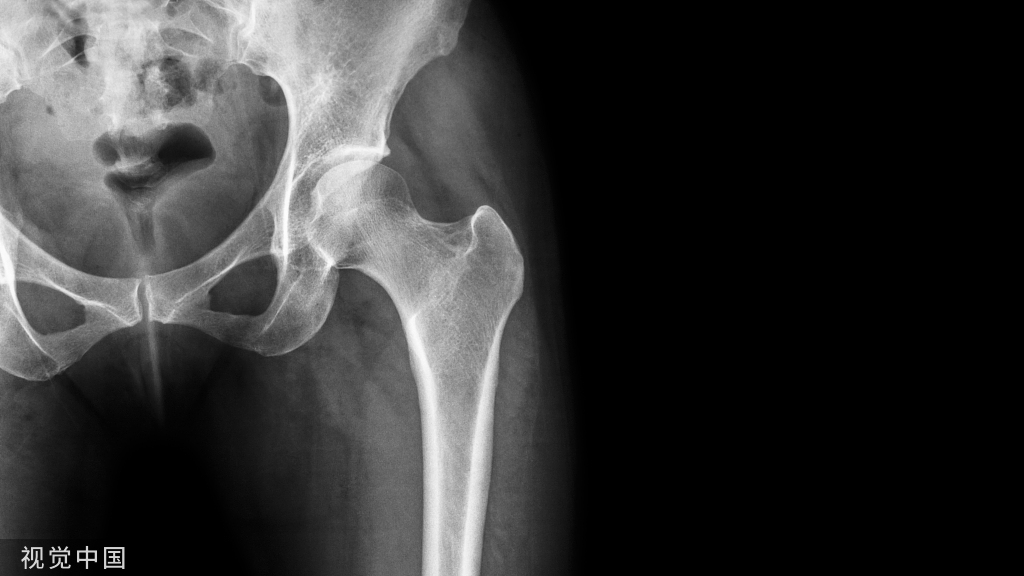

髋部骨一、骨盆:⒈髂骨   2.坐骨   3.耻骨二、股骨

股骨:股骨头、股骨颈、大转子、小转子、转子间线、转子间嵴、臀肌粗隆

髋关节构成 :   髋臼与髋臼唇 、股骨头、髋的横韧带

髋关节特点:1. 头大、窝深2. 关节囊厚而坚实3. 关节囊有许多韧带增强,如髂股韧带等4. 关节囊内有股骨头韧带